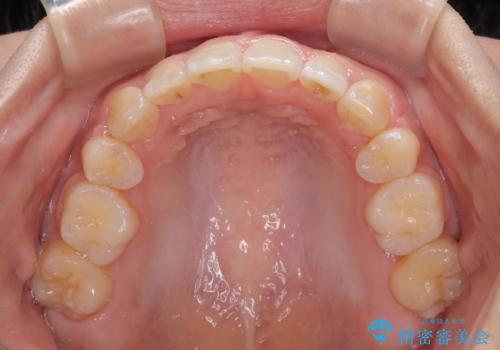

上下の前歯が接触する仕上がりとなったので、横顔の印象が大幅に改善されました。